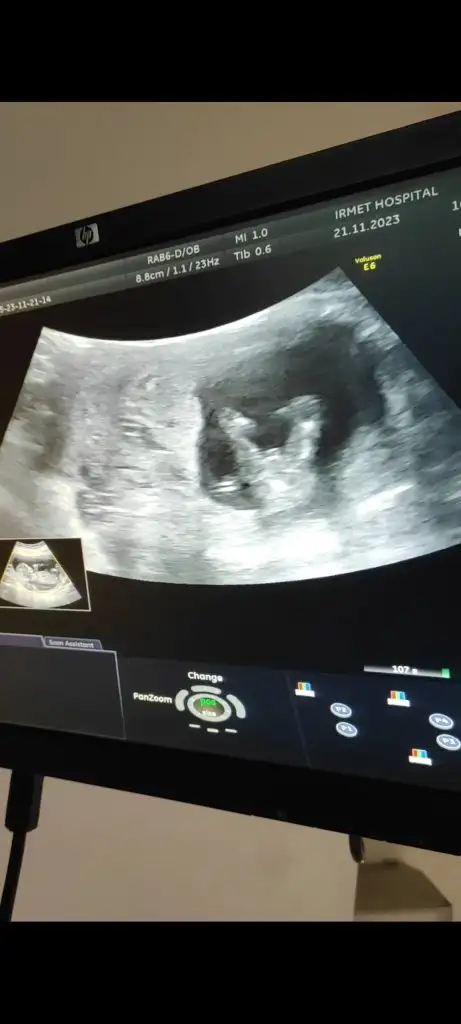

Kızlar son adete göre 11+5 ultrasona göre 12+3 günlük nub teorisi diye birşey varmış anlayan varmı bugün doktor tahminde bulundu ama net görmedim dedi 1 ay sonra randevum var. Bu arada çok şükür herşey yolunda ❤️